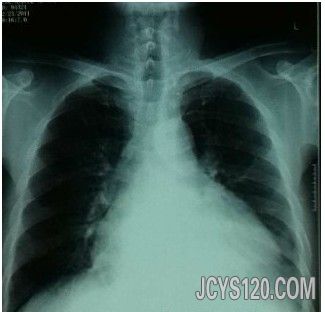

胸片;

查体,T36.2. R22次 P105次 BP100/80. 神志清楚,精神萎靡,成慢性病容,口唇轻度紫绀,甲状腺无肿大,颈静脉略怒张。双肺底部可闻及湿罗音,心尖搏动在第六肋间左锁骨中线外1.5CM处,第一心音有些低钝,心率105次/分。在心尖和三尖瓣可闻及收缩期吹风样杂音,II/6;叩诊心浊音界向两侧增大。上腹部略涨;肝在肋缘下1CM,肝颈静脉逆流征阳性,尿少,叩诊未见移动性浊音,脚踝处有轻度凹陷性水肿。